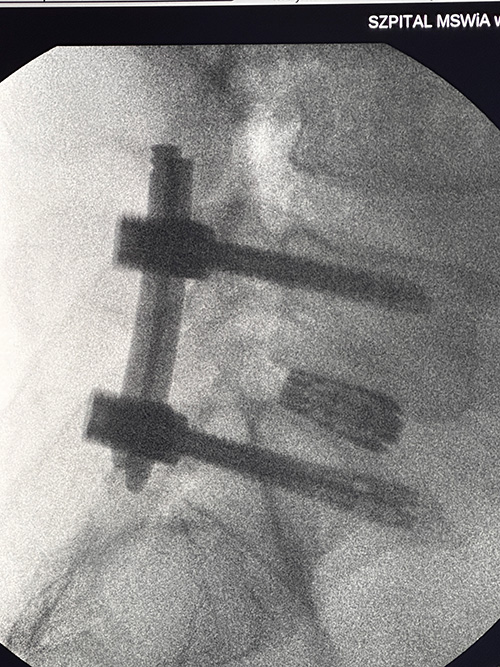

Szpital MSWiA w Kielcach ma na swoim koncie liczne sukcesy, a dr Arkadiusz Granek po raz kolejny przyczynia się do jednego z nich, wykonując – z pełnym sukcesem – jedną z pierwszych w Europie operacji w pełni endoskopowej stabilizacji kręgosłupa odcinka lędźwiowego.

Dzięki tej metodzie chory po wcześniejszej dekompresji L5/S1 z bólem korzeniowym po lewej stronie, obecnie podaje ustąpienie objawów.